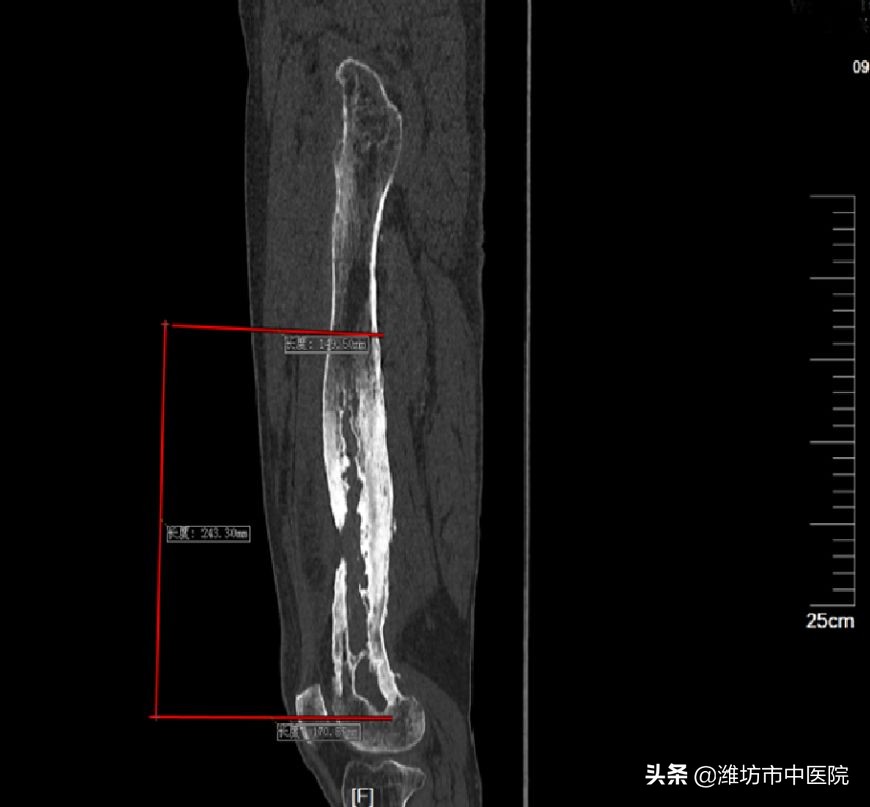

老人的股骨骨髓炎已有50多年,极为少见,股骨大量被侵蚀、破坏,死骨大量形成,范围占据大腿长度的2/3,达到了罕见的25cm,远端部分已经接近膝关节,既要清除病灶,又要保护膝关节,还要保证股骨的强度,避免骨折,治疗起来难度极大,对专业程度要求极高。患者入院后,张荣峰主任仔细研究影像学资料,准确判断感染病灶的范围,结合上千例骨髓炎的治疗经验,为患者制定了个体化的精准治疗方案,并且融入近几年骨感染治疗的先进理念和技术。经充分准备,在冯云华主任的大力支持下,在手术室人员的密切协作下,于10月4日进行了手术治疗。虽然手术过程繁琐、复杂,但是手术极其顺利、术中出血很少。